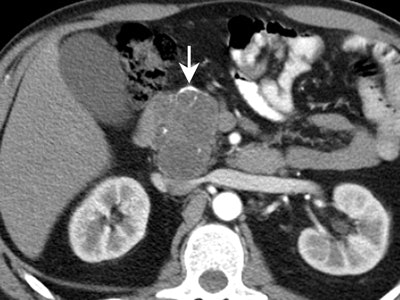

![]() |

| MRI shows multilocular serous cystadenoma (on T1 breath-hold the fine septations are visible). |